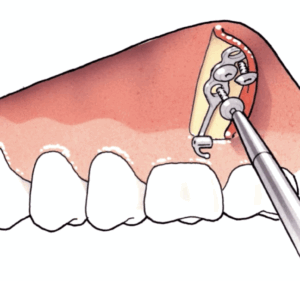

De platen zijn stevig bevestigd met 2 (in de onderkaak) of 3 (in de bovenkaak) schroeven op een veilige afstand van de wortels van de tanden. Meestal worden de bovenste platen met monocorticale schroeven, 2,0mm diameter en 5mm lengte voor de onderste schroeven en 7mm lengte voor de bovenste schroef op de infra-zygomatische top van de bovenkaak gestoken. In de onderkaak worden de platen meestal tussen de hoektand en de laterale snijtand geplaatst. Voor sommige indicaties kunnen ze ook tussen de eerste molaar en de tweede bicuspide worden geplaatst.

Bestaat uit een miniplate met 2 of 3 gaten, een verbindingsstang en een bevestigingseenheid met een blokkeerschroef. Het ontwerp van de cilindrische bevestigingseenheid maakt het mogelijk om allerlei soorten draden te bevestigen om verbinding te maken met het vaste apparaat.